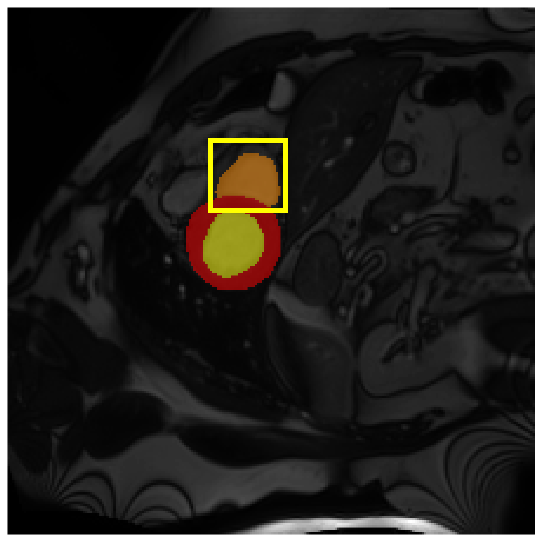

Medical image segmentation plays a critical role in various diagnostic workflows, as it enables accurate delineation of anatomical structures and pathological regions, thereby enhancing disease interpretation, treatment planning, and outcome prediction. Jang et al. [1] has demonstrated that improved segmentation performance can lead directly to reduced diagnostic error rates and increased clinician confidence. Building on the remarkable success of deep learning across diverse domains [2, 3, 4, 5], recent progress in medical image segmentation has been primarily driven by deep learning. Since the introduction of U-Net [6], segmentation methods have rapidly evolved, with convolutional neural networks (CNN)-based models [7, 8, 9] and Transformer-based models [10, 11, 12] showing superior performance in computed tomography (CT) and magnetic resonance imaging (MRI) segmentation. However, various challenges such as blurriness, noise, and low contrast often hinder the accurate diagnosis of diseases. Applying various image enhancement techniques to generate an enhanced image from the input can alleviate this problem, as existing methods have demonstrated improved segmentation accuracy [13, 14, 15]. Nevertheless, input images may unintentionally lose crucial information contained in the original image during enhancement. As a result, the segmentation model suffers from performance degradation (Fig. 1(a) and (b)). Therefore, we argue that it is crucial to leverage the advantages of both the original and enhanced images through image fusion strategies.

4.3.2 Visual Comparisons

Visualization of our method on the Synapse and ACDC datasets is shown in Fig. 3(a) and Fig. 3(b). For the Synapse dataset illustrated in Fig. 3(a), FCT failed to accurately segment SM and GB, while MERIT achieved precise segmentation of SM but struggled with GB. In contrast, our method achieved accurate segmentation of both SM and GB. Regarding the ACDC dataset shown in Fig. 3(b), while previous methods achieve comparable segmentation of the Myo and LV to the GT, they exhibit noticeable errors on the RV, including invasion into adjacent organs and misrecognition. On the other hand, our method accurately segments across all three structures Myo, LV, and RV, performing as precisely as the GT. We demonstrate the superiority of our method quantitatively and qualitatively.